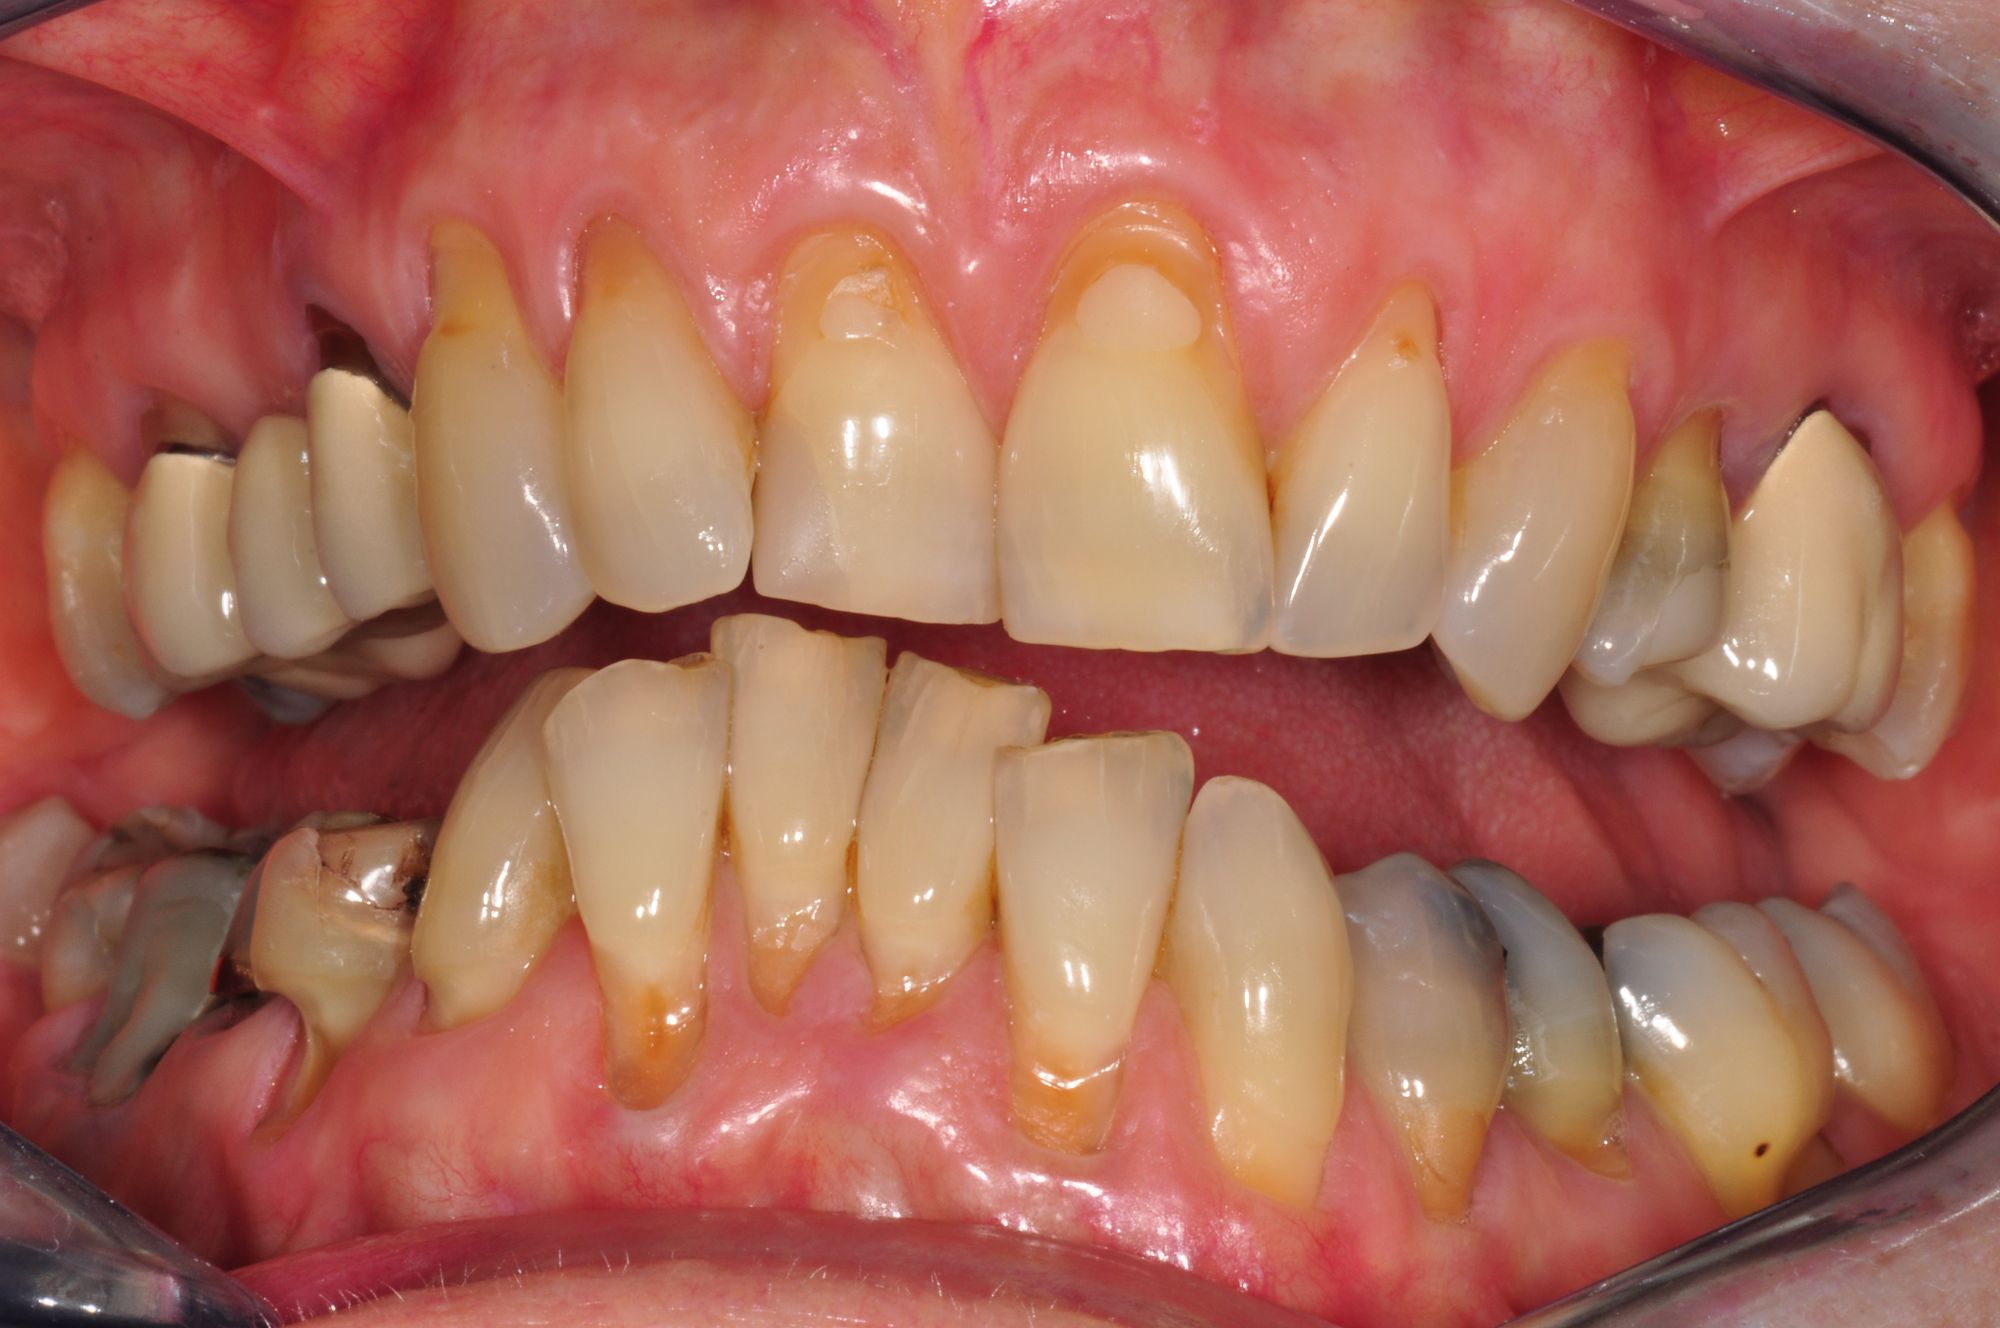

Parodontitis, unschöne Kronen, drohender Zahnverlust

Vorher: Parodontitis, unschöne Kronen, drohender Zahnverlust

Festsitzender Ersatz auf Implantaten

Nachher: Festsitzender Ersatz auf Implantaten